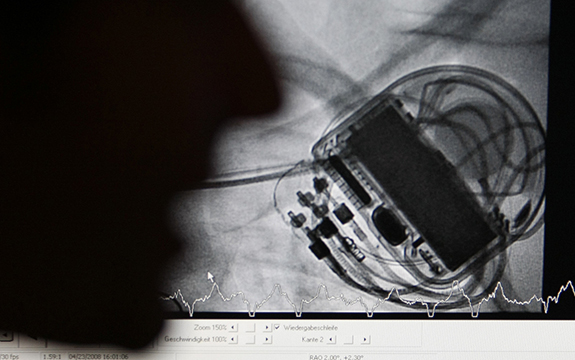

The US Food and Drug Administration (FDA) recently recalled approximately 465,000 pacemakers made by the company Abbott’s (formerly St. Jude Medical) that were vulnerable to hacking, but the situation points to an ongoing security problem.

The reason for the recall? The devices can be remotely “hacked” to increase activity or reduce battery life, potentially endangering patients. According to reports, a significant portion of the pacemakers are likely to be installed in Australian patients.

The vulnerability of the pacemaker appears to be that someone with “commercially-available equipment” could send commands to the pacemaker, changing its settings and software. The “patched” version prevents this – it only allows authorised hardware and software tools to send commands to the device.